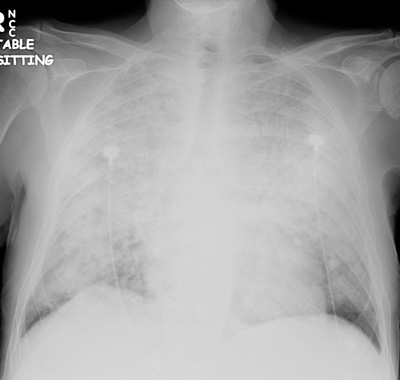

Initial CXR for the case found here:

(CXR source: http://www.radiology.vcu.edu/programs/residents/quiz/pulm_cotw/PulmonConf/09-03-04/68yM%2008-03-04%20CXR.jpg)